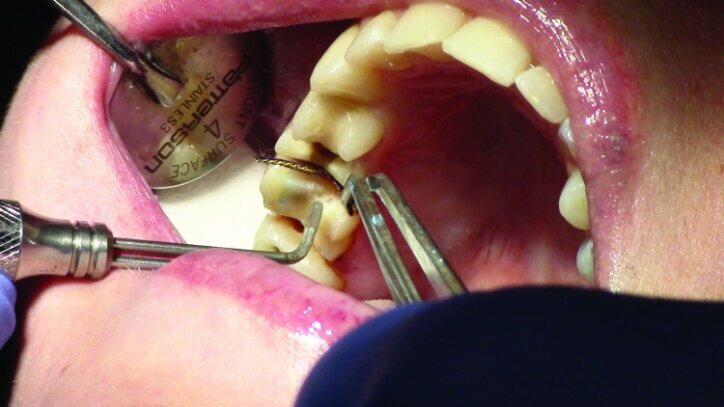

Tissue management was obtained with ViscoStat Clear, gingival haemostatic gel, 25 percent (m/m) aluminum chloride (Figs. 16 & 17). Gingival retraction was obtained using a two-cord system. First, a #00 size cord from Ultradent was placed on the mesial and distal of both preparations (Figs. 18 & 19).

Additional haemostatic gel was used prior to the second cord. The second cord was #2 size cord from Ultradent (Figs. 20 & 21a). A minimum of four minutes with both cords in place is needed for adequate retraction of the soft tissue (Fig. 21b).